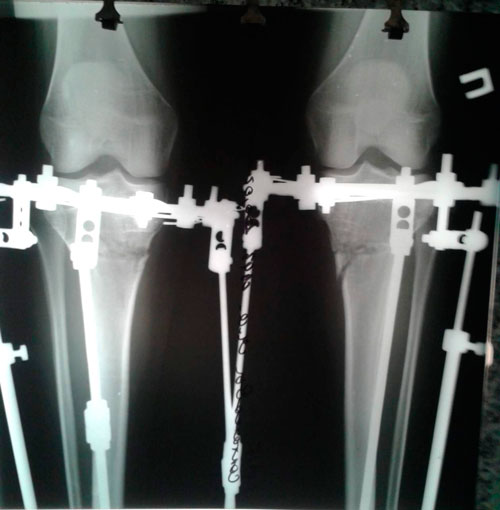

РЕНТГЕН В 20  ДНЕЙ ПОСЛЕ ОПЕРАЦИИ